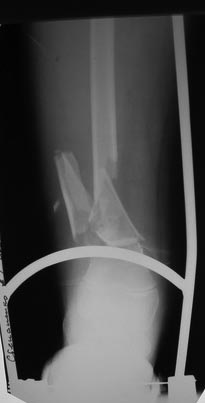

Переломы оскольчатые обеих бёдер в н/3, открытые. Раны ушиты в отличном

состоянии.

На одном бедре межмыщелковый перелом и там мыщелки немного разъехались.

Голень там тоже сломана в н/3 обе кости. Снимок голени в боковой

проекции сделан не был.